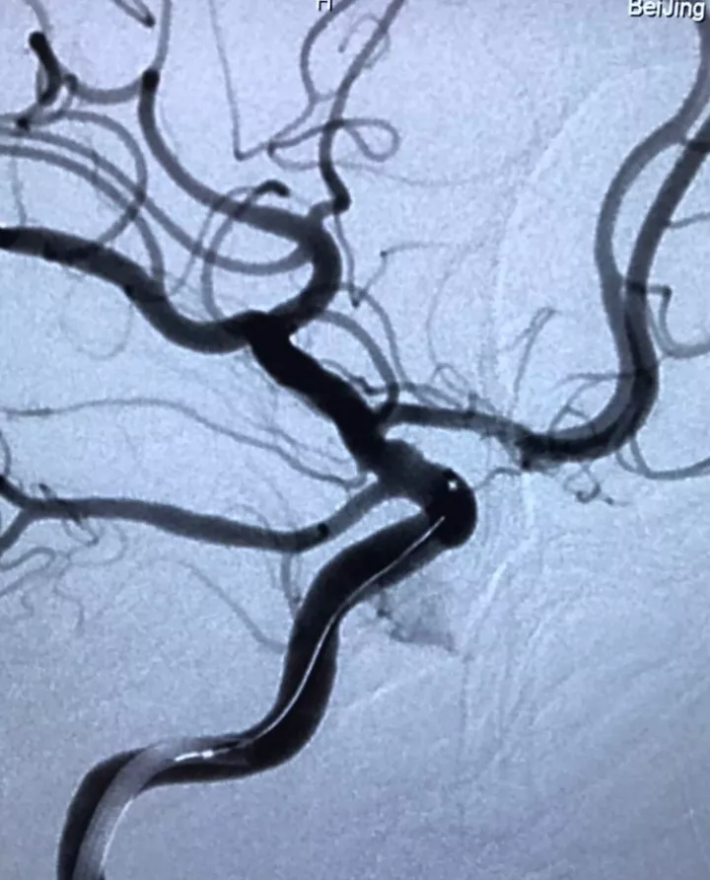

微导丝头端进入瘤颈